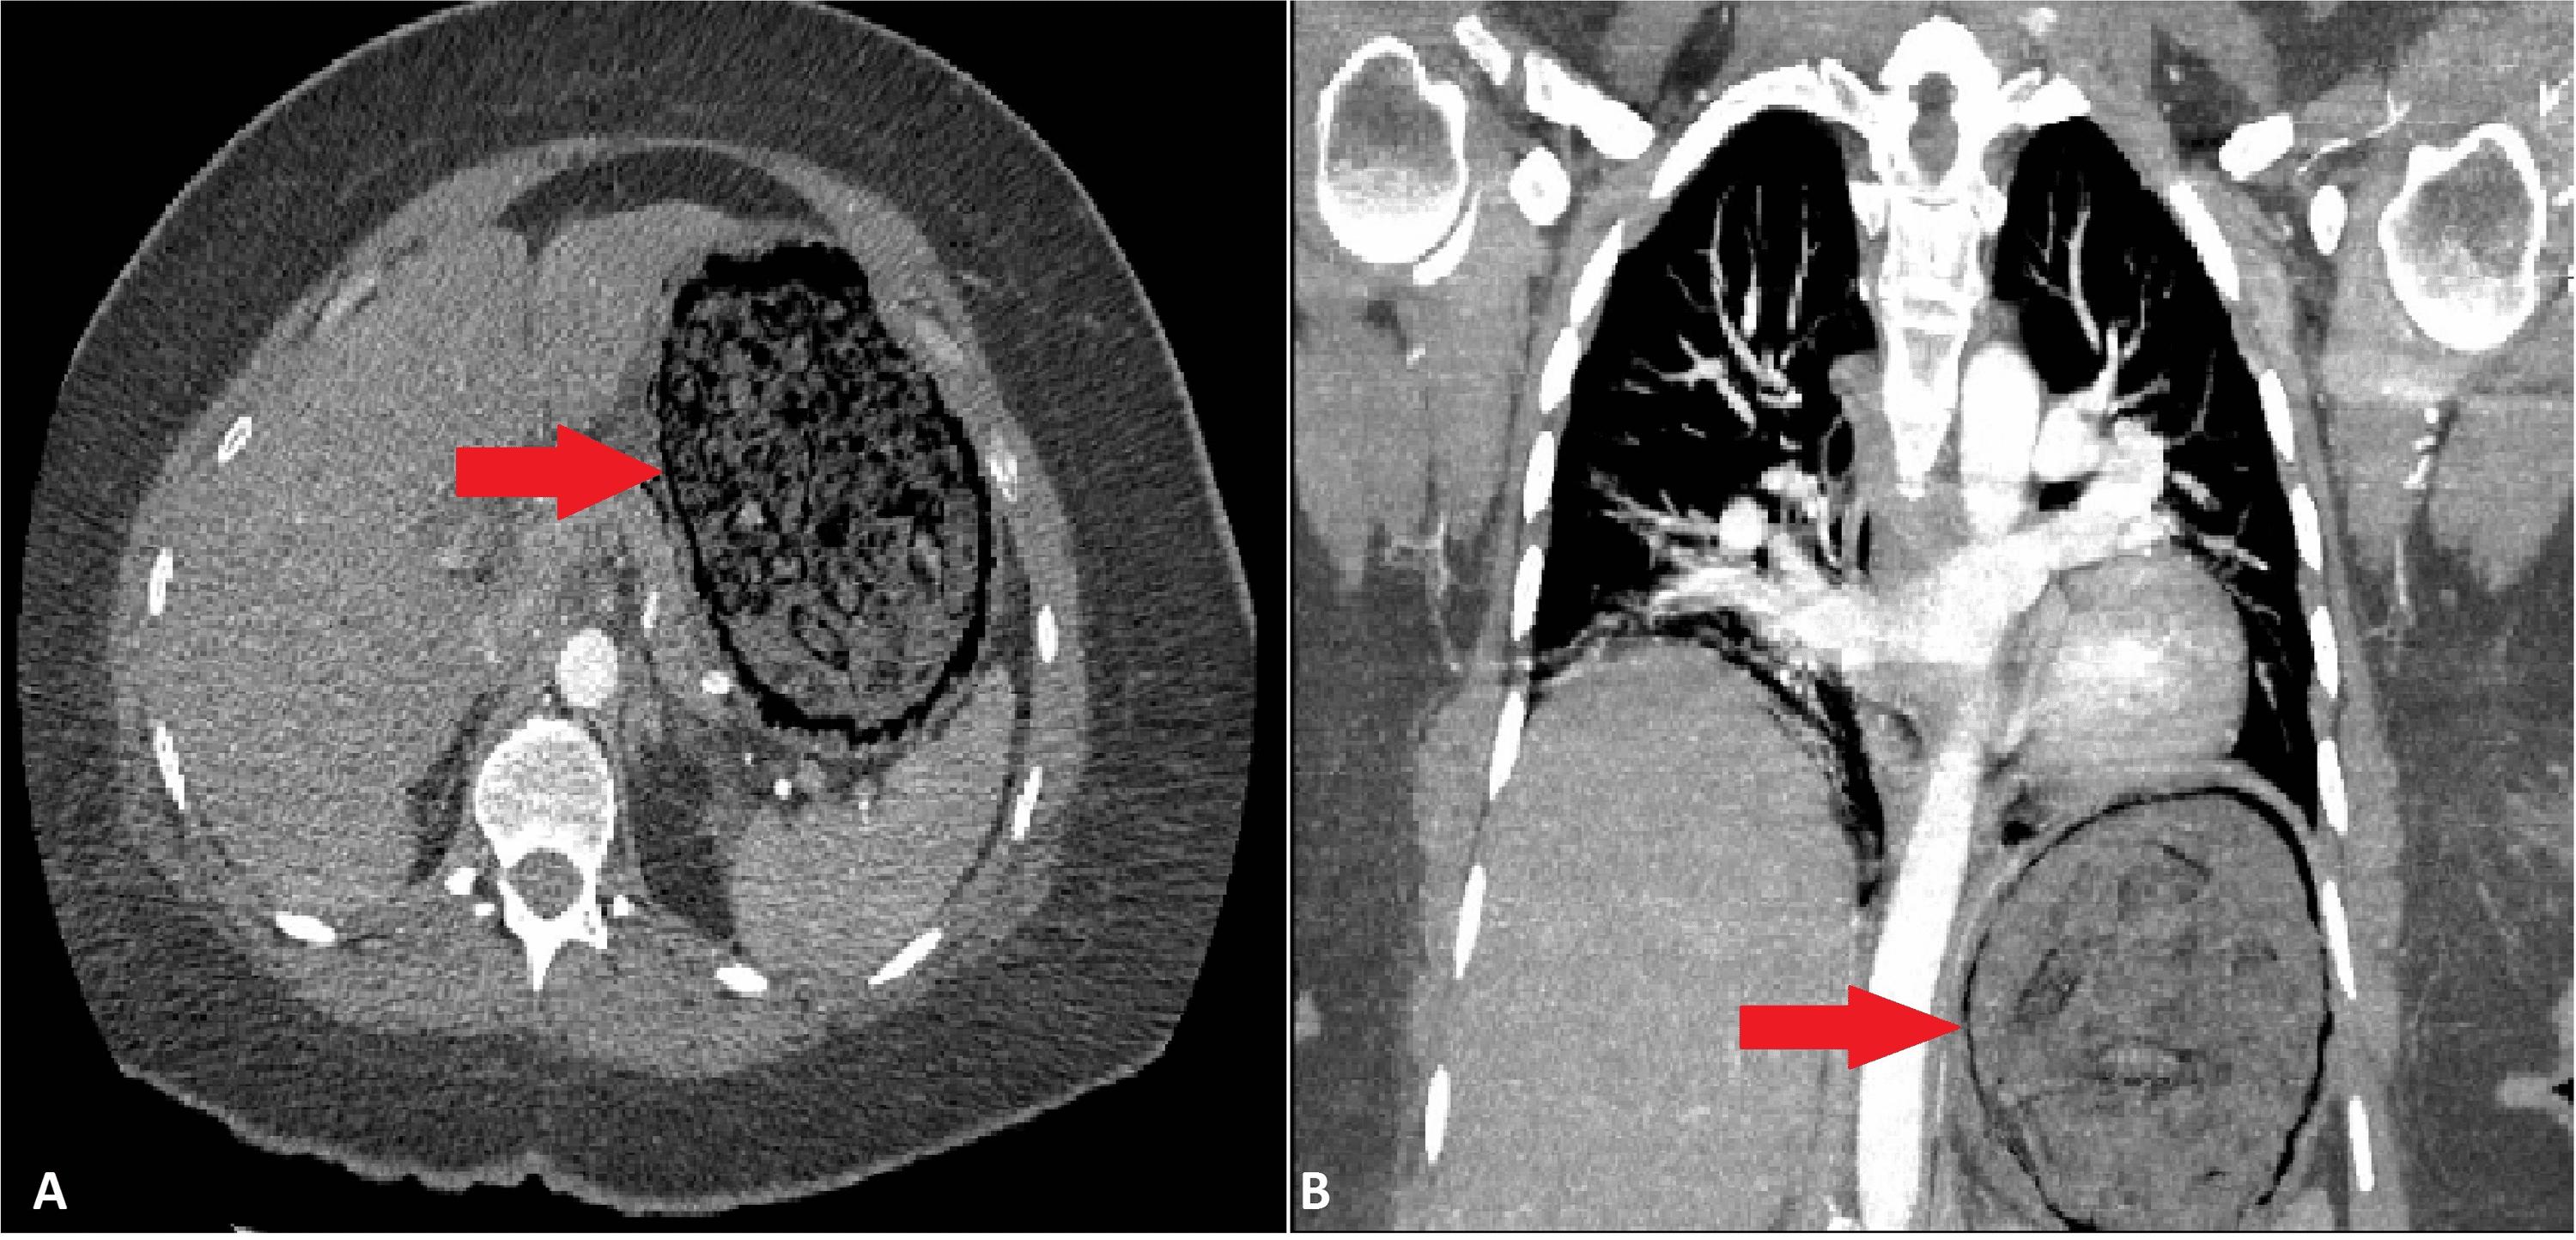

(PDF) Emphysematous Gastritis Secondary to Gastric Mucormycosis in A Case Report Of Emphysematous Gastritis 1 as in our case, diabetes mellitus, malnutrition, and renal failure. Our case was notable in that appropriate and prompt conservative treatments prevented fatal outcome and led to disappearance of hepatic portal venous gas, and this was the. Emphysematous gastritis (eg) is an exceedingly rare cause of severe abdominal pain with an associated mortality reported at greater. Recent case literature. Case Report Of Emphysematous Gastritis.

(PDF) Emphysematous Gastritis Associated with Invasive Gastric Case Report Of Emphysematous Gastritis 1 as in our case, diabetes mellitus, malnutrition, and renal failure. Recent case literature shows a trend towards conservative management for emphysematous gastritis with several. Emphysematous gastritis (eg) is a rare condition characterized by air within the. Emphysematous gastritis (eg) is an exceedingly rare cause of severe abdominal pain with an associated mortality reported at greater. Our case was notable. Case Report Of Emphysematous Gastritis.